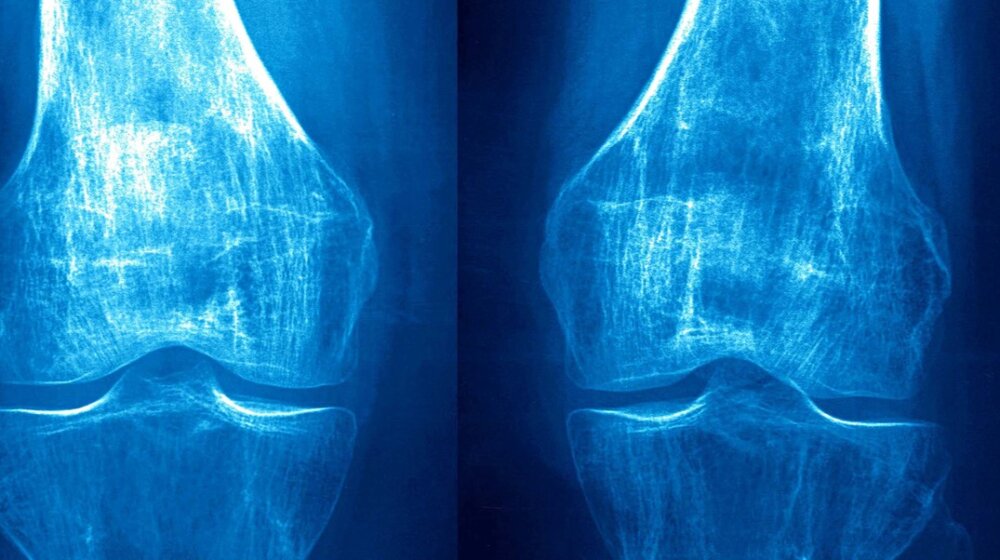

Osteoporoza, foto: CAVALLINI JAMES / BSIP / Profimedia

Osteoporoza, foto: CAVALLINI JAMES / BSIP / ProfimediaKalcijum je mineral koji aktivno učestvuje u održavanju normalne funkcije srca, nerava, mišića i ključan je za zdravlje kostiju. Ima važnu ulogu i kada je reč o lečenju i prevenciji brojih bolesti koje uglavnom i nastaju sa manjakom ovog minerala u organizmu – osteoporoze i tetanije.

Osteoporoza je bolest koja se manifestuje smanjenjem gustine kostiju, zbog čega one postaju porozne. Do poroznosti kostiju dolazi sa smanjenjem gustine kostiju i koštanog tkiva što je u direktnoj vezi sa smanjenjem količina kalcijuma.

Krhke i porozne kosti pojačano su osetljive na različite fizičke stresove (udarce, padove). Osteoporoza je jedan od glavnih uzroka ozbiljnog invaliditeta starijih ljudi. Prelom kuka uzrokovan osteoporozom zahvata jednu od tri žene i jednog od pet muškaraca u dobi do 85 godina.